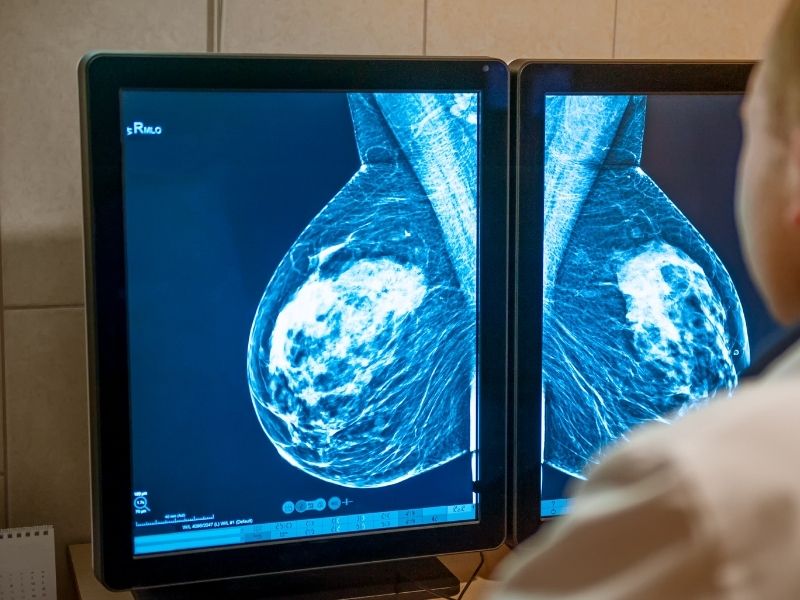

Mamografi, memenin düşük doz X ışını kullanılarak görüntülenmesini sağlayan bir yöntemdir ve meme taraması denildiğinde en sık başvurulan incelemelerden biridir. Mamografi, özellikle belirli yaşın üzerindeki kişilerde tarama amaçlı kullanım için güçlü bir araçtır. Bunun temel nedeni, bazı bulguların muayene ile ele gelmeden ya da belirti vermeden önce mamografide saptanabilmesidir. Bu özellik, meme taraması ile erken tanı hedefinin temel taşlarından biridir.

Mamografinin ne zaman tercih edileceği, kişinin yaşına ve risk durumuna göre değişir. Meme dokusunun yoğun olduğu genç yaşlarda mamografinin duyarlılığı değişebileceği için, genel cerrahi uzmanı çoğu zaman mamografiyi ultrason gibi tamamlayıcı yöntemlerle birlikte değerlendirebilir. Mamografi sonucunda şüpheli bir alan görülmesi her zaman kötü huylu bir durumu göstermez, ancak meme taraması zincirinde bir sonraki adımın belirlenmesini sağlar. Bu nedenle mamografi sonucu, tek başına değil klinik değerlendirme ve gerekirse ek görüntüleme ile birlikte ele alınmalıdır.